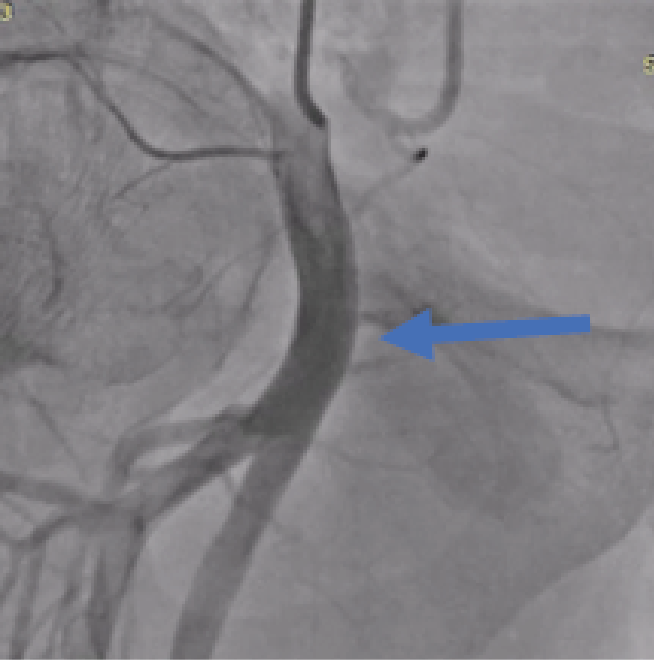

A 42-year-old male who underwent angiography with no obstructive disease found. he was discharged home on the same day but returned to the hospital for Symptoms in- clude groin swelling, unusual pain, bruising, skin changes, neuropathy from femoral nerve compression and claudica- tion from embolization or arterial compression. On examina- tion pulsatile mass in his right groin with a bruit. Angio CT suggested large pseudoaneurysm 7x8 cm in right femoral artery [figure1]. Angiography to his right common femoral artery revealed large pseudoaneurysm [2]. With a contra- lateral sheath placed in the left common femoral artery, the pseudoaneurysm was entered through the neck using 0.014 inch coronary wire. A micro introducer needle was then used to enter the pseudoaneurysm A 0.014-inch wire was then ad- vanced through the neck of the pseudoaneurysm retrograde- ly into the external iliac artery. The micro introducer sheath was then advanced into the pseudoaneurysm over the wire and retrogradely into the external iliac artery. The 0.014-inch wire was exchanged with a 0.035-inch Whole wire. The star closure device was then deployed with the anchor against the pseudoaneurysm neck with subsequent thrombosis of the pseudoaneurysm [figure 3]. Control Angiography through the contralateral sheath showed complete occlusion of the neck with no compromise to the common femoral artery.

Figure 1: CT angiography: large pseudoaneurysm in right femoral artery